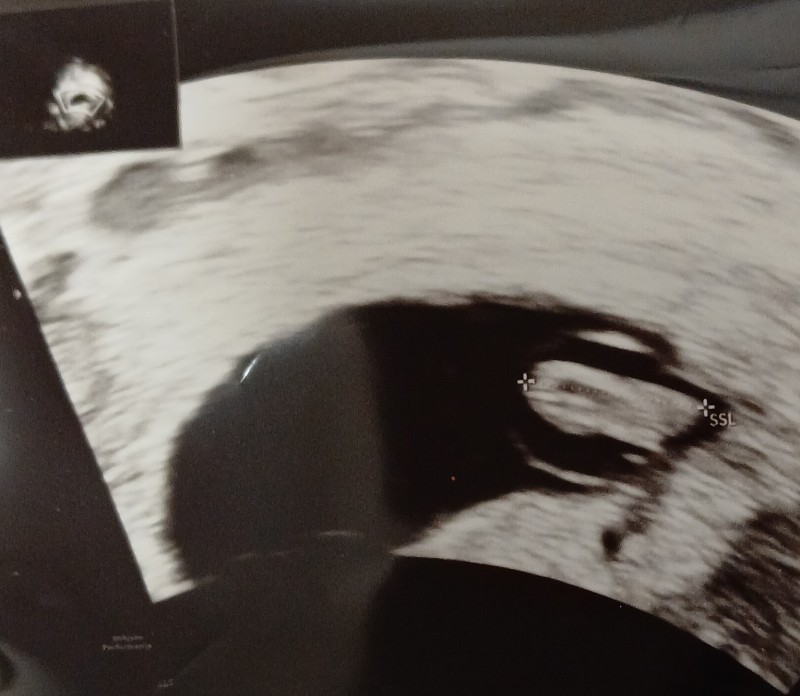

image

Bana da tahminde bulunabilir misiniz lütfen kese şekli vs vajinal ultrason yapıldı 7+1 burada

Nub çok yatay çıkmış diklik yok o yüzden kız dedım